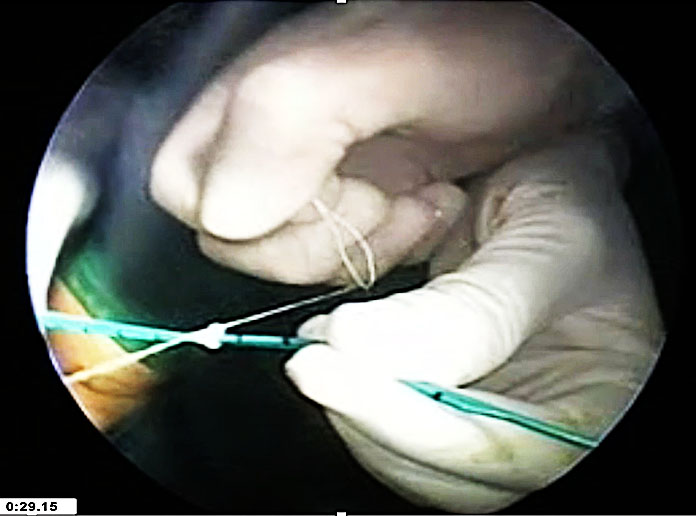

A unique laparoscopic technique for VVF repair involves passing a ureteric catheter through the vaginal opening of the fistula and retrieving it cystoscopically through the urethra. The two ends of the catheter are tied together, eliminating the need for a catheter within the bladder during dissection. Laparoscopic dissection is then performed, carefully separating the tissue planes laterally until the fistula is visualized, guided by the ureteric catheter. Adequate dissection distal to the fistula opening is essential to mobilize enough healthy bladder tissue for closure. Once this is achieved, the ureteric catheter is cut and removed. The vaginal side of the fistula is closed using interrupted 1–0 Vicryl sutures. The bladder defect is then closed in two layers: a continuous suture with V-Loc, followed by a second layer of interrupted 1–0 or 2–0 Vicryl sutures (Figure 20). If necessary, the bladder can be filled with 200–250 ml of diluted methylene blue to test for leakage.

Finally, a Foley catheter is placed per urethra for 3 weeks before removal.

(a) |

(b) |

(c) |

(d) |

(e) |

(f) |

(g) |

(h) |

(i) |

(j) |

20

(a) Vesicovaginal fistula noted on cystoscopy. (b) Mixter forceps introduced through the fistulous tract from the vagina. (c) Ureteric stent passed through the fistula into the vagina. (d) Stent pulled out through the vagina with one end seen through the urethra. (e) Vaginal and urethral ends of the stent tied. (f) Further dissection opens up the bladder and fistulous area. (g) Stent cut from the vaginal end. (h) Vaginal part closed with barbed V-Loc with stent aiding in bladder retraction. (i) Bladder edges refreshed for proper mobilization. (j) Bladder closed in a double layer.